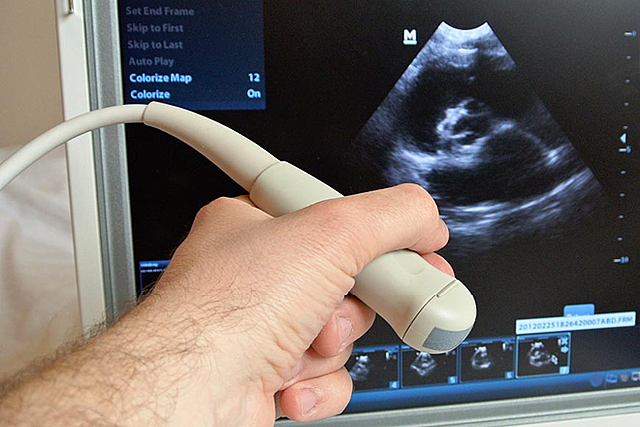

• Ultrasonido

Ultrasonido

El uso del ultrasonido de alta frecuencia en problemas marítimos se inició en la primera guerra mundial sin embargo, no fue hasta finales de los 70 que se lograron los equipos a tiempo real tal como los conocemos actualmente.